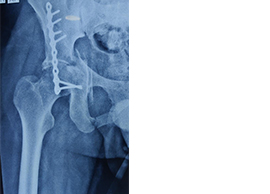

These fractures require urgent and precise surgical fixation to achieve the ultimate outcome. We at our centre routinely perform such surgeries.

Case 2:- Pubic Diastasis